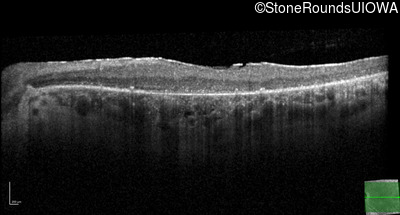

Optical Coherence Tomography - Left - 10/200

Exemplar / OCT Stack

OCT Stack